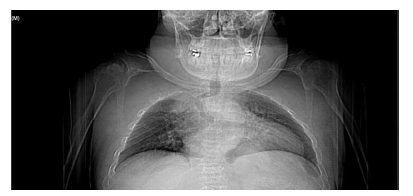

En la mayoría de los niños se pueden observar características dentales como cúspides puntiagudas, incisivos en forma de pala, esmalte delgado y superficies bucales con hoyos. Además, la ATM puede verse afectada con una reabsorción severa de la cabeza del cóndilo36 (Figuras 9-11).